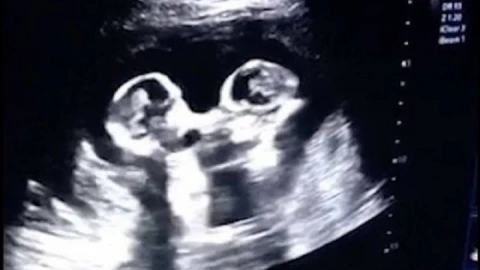

Анасының құрсағынан УКС арқылы түсірілген егіз сәбилердің төбелесі көпшілікті таңғалдырды.

28 жастағы Тао есімді қытайлық азамат жүкті әйелінің құрсағындағы егіз балалардың видесын жариялады. Кадрдан егіз қыздардың бір-бірін жұдырығымен ұрып жатқаны байқалады. Бұл көрініс балалардың әкесін күлкіге қарық қылды.

Ал, дәрігерлер мұның қауіпті екенін айтады. Әдетте егіздер құрсақта өзіндік амниотилық қабында болады. Бұл бір-бірінен бөліп тұрады. Ал, бұл жолы егіздер бір ғана амниотикалық қапта. Бұл сирек кездеседі. Соққыдан екеуі немесе бірі өлі тууы мүмкін. Ондағы негізгі қауіп - бала тыныс алатын кіндіктің қысылып қалуы. Мұндай жағдайда балалардың тірі қалуы 50 пайыз.

Не дегенмен егіз қыздар аман-есен өмірге келді. Екеуі де сау. Бірі 1630, бірі 1950 грамм салмақта.

Әкесі қыздарының тумай жатып жұлдыз болып кетерін білмегенін айтады. Ол УКС арқылы егіздердің бір-бірін құшақтап жатқанын да көрген.